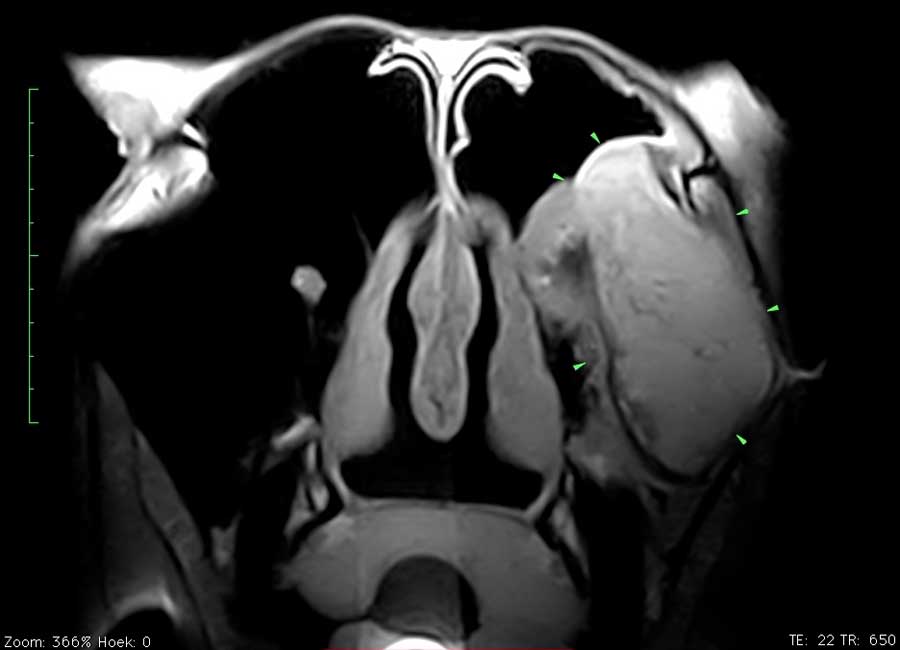

Dit paard had sinds enkele weken een unilaterale bloederige neusvloei. Op endoscopisch onderzoek was slechts een minimale afwijking ter hoogte van het linker ethmoid te zien. Radiografisch onderzoek toonde echter een grote massa in de sinus. Er werd beslist een pre-operatieve MRI uit te voeren om de operatie te plannen en ook de prognose beter te kunnen inschatten. Het ethmoid hematoom (PEH) bleek een groot deel van de linker sinus ingenomen te hebben.